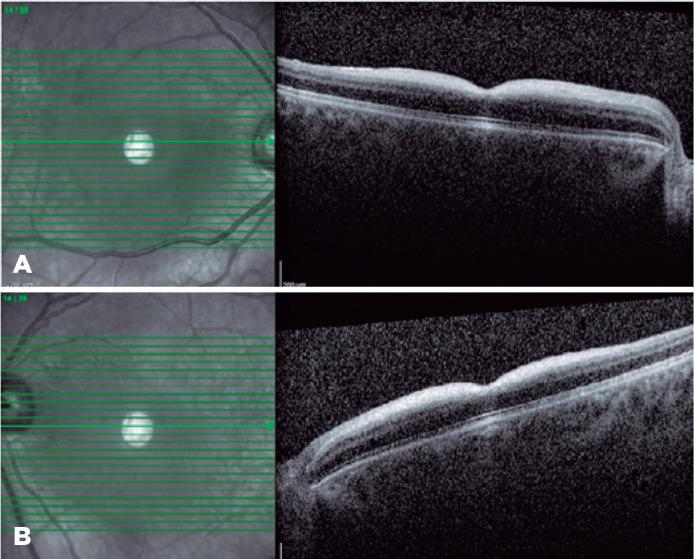

This report presents the optical coherence tomography findings and a new NEU1 mutation in bilateral macular cherry-red spot syndrome associated with sialidosis type 1. A 19-year-old patient with a macular cherry-red spot underwent metabolic and genetic analyses supported by spectral-domain optical coherence tomography. Fundus examination revealed bilateral macular cherry-red spot. Spectral-domain optical coherence tomography revealed increased hyperreflectivity in the retinal inner layers and the photoreceptor layer in the foveal region. The genetic analysis detected a new NEU1 mutation, which caused type I sialidosis. In cases with a macular cherry-red spot, sialidosis should be included in the differential diagnosis, and NEU1 mutation should be screened. Spectral-domain optical coherence tomography alone is not sufficient in the differential diagnosis because childhood metabolic diseases may exhibit similar signs.

本报告介绍了光学相干断层扫描结果和 1 型神经氨酸酶 1(NEU1)突变与双侧黄斑樱桃红斑点综合征的关系,该综合征与唾液酸贮积症 1 型有关。一名 19 岁患者因黄斑樱桃红斑点接受了代谢和遗传分析,并结合频域光学相干断层扫描进行支持。眼底检查显示双侧黄斑樱桃红斑点。频域光学相干断层扫描显示视网膜内层和黄斑区光感受器层的高反射性增加。基因分析发现了一个新的 NEU1 突变,导致 1 型唾液酸贮积症。在有黄斑樱桃红斑点的病例中,唾液酸贮积症应包括在鉴别诊断中,并应筛查 NEU1 突变。频域光学相干断层扫描本身不足以进行鉴别诊断,因为儿童期代谢疾病可能表现出相似的体征。